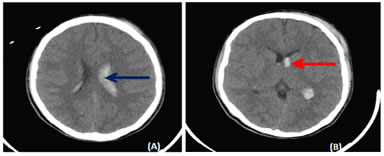

Figure 10: Axial NECT scan (a-b): (a-b) A 15-year old boymet with a road traffic accident. Hemorrhage in caudate nucleus (red arrow) on left sidewith breakthrough hemorrhage into the bilateral lateral ventricles (blue arrow).